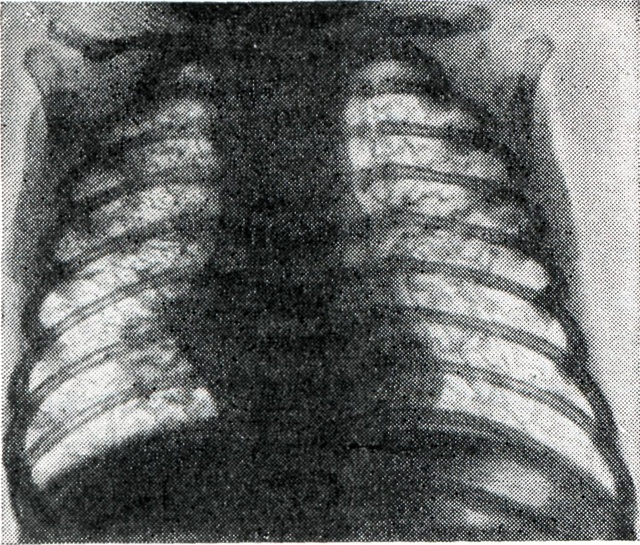

Иногда наблюдается эозинофилия до 15% . Биохимические, бактериологические, вирусологические, серологические данные без особенностей. В течение болезни развивается дыхательный аци¬доз, снижается насыщение кислоро¬дом крови. Приблизительно на 3-й неделе появляются типичные для В.— М. с. изменения на рентгенограммах: базальная и распространённая эмфизема, симметричное усиление лёгочного рисунка в области корней (рисунок), утолщение интерстициальных перегородок, увеличение размеров сердца; типична «нодозно-ретикулярная сетка» — рентгенологическое отображение незрелой лёгочной ткани. Сетка состоит из теней нередуцированной и содержащей эмбриональные волокна соединительной ткани, между которыми расположены заполненные воздухом незрелые концевые отделы дыхательных путей. Сетка включает очаги — тени нерасправившихся постнатально долек лёгких и мелких неразвитых сосудов. Присоединение расплывчатых затемнений указывает на развитие отечно-геморрагического синдрома, который резко ухудшает прогноз заболевания. Постепенное созревание лёгочной ткани, отмечаемое рентгенологически по восстановлению нормальной структуры лёгочного рисунка, ведёт к благоприятному исходу.